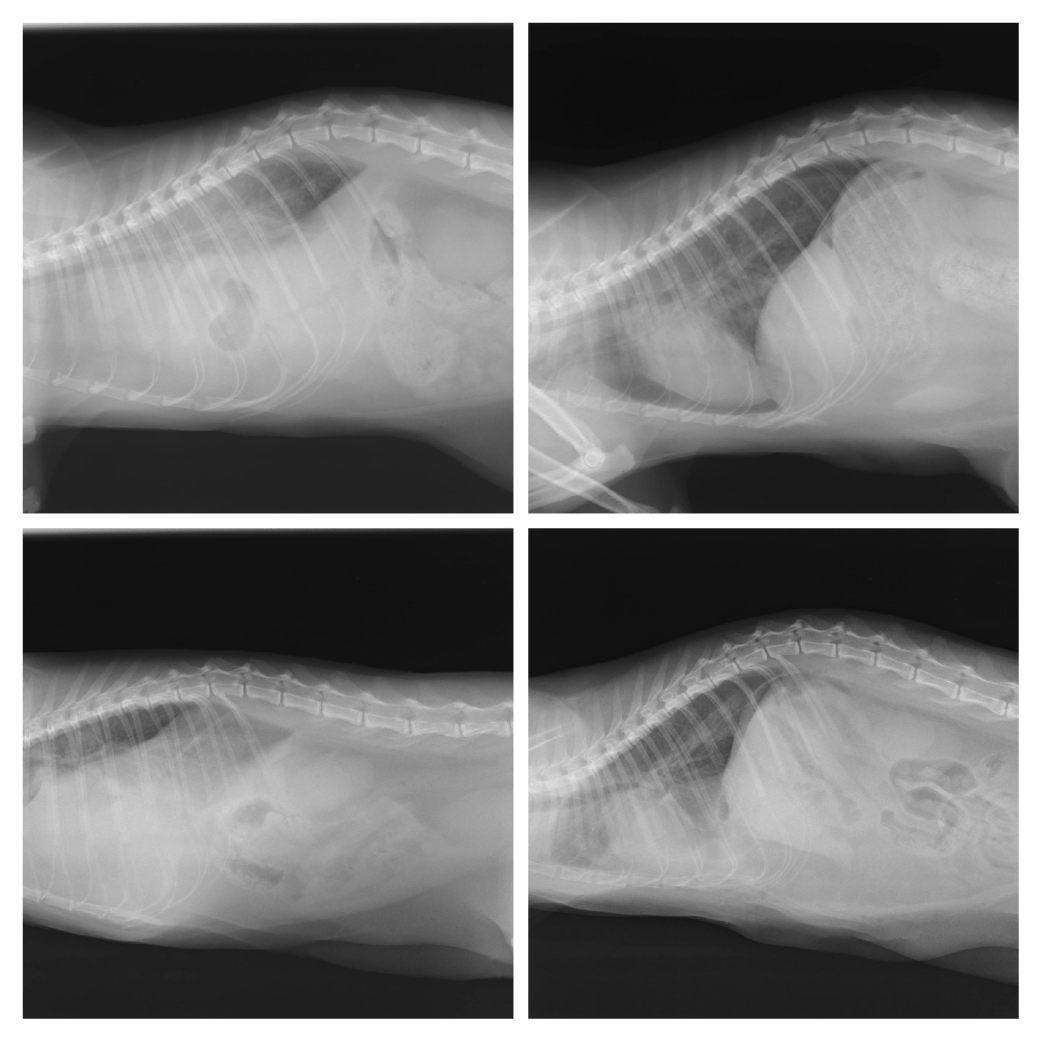

Hoje apresentamos mais 2 casos interessantes que nos deixam muito felizes. São daquelas situações que, numa gíria da veterinária, costumamos dizer que, quando aparecem, acabam por ser sempre aos pares (aqueles casos pouco frequentes que, de repente, se multiplicam). Curiosamente, estes 2 casos foram-nos referenciados pela Dra. Cátia Pereira da Ilha de São Jorge, no final do passado mês de setembro. Um gato e uma gata com possível história de traumatismo (possível atropelamento), com dificuldades respiratórias e auscultação pulmonar e cardíaca abafadas. No raio-x foi possível confirmar a suspeita de hérnia diafragmática. Esta situação, que também pode ser congénita, ocorre na maior parte das vezes resultante de traumas que resultam no rompimento do diafragma (músculo que separa as cavidades toráxica e abdominal), permitindo que as vísceras abdominais possam ocupar espaço no tórax e assim diminuir de forma mais ou menos séria a capacidade respiratória do animal, dependendo do volume que é ocupado. Ambos os animais foram submetidos a uma intervenção cirúrgica delicada, não isenta de riscos e que obriga a ventilação assistida. Felizmente ambos recuperaram muito bem e voltaram a casa. Nas fotos é possível observar à esquerda as imagens com hérnia diafragmática, em que nem é possível identificar a silhueta cardíaca e à direita no pós cirúrgico, já em processo de recuperação ainda com ligeiro grau de pneumotórax e efusão que se resolveram. Obrigado à Dra. Cátia e aos donos destes meninos pela confiança.

Hérnia diafragmática 13 outubro 2014